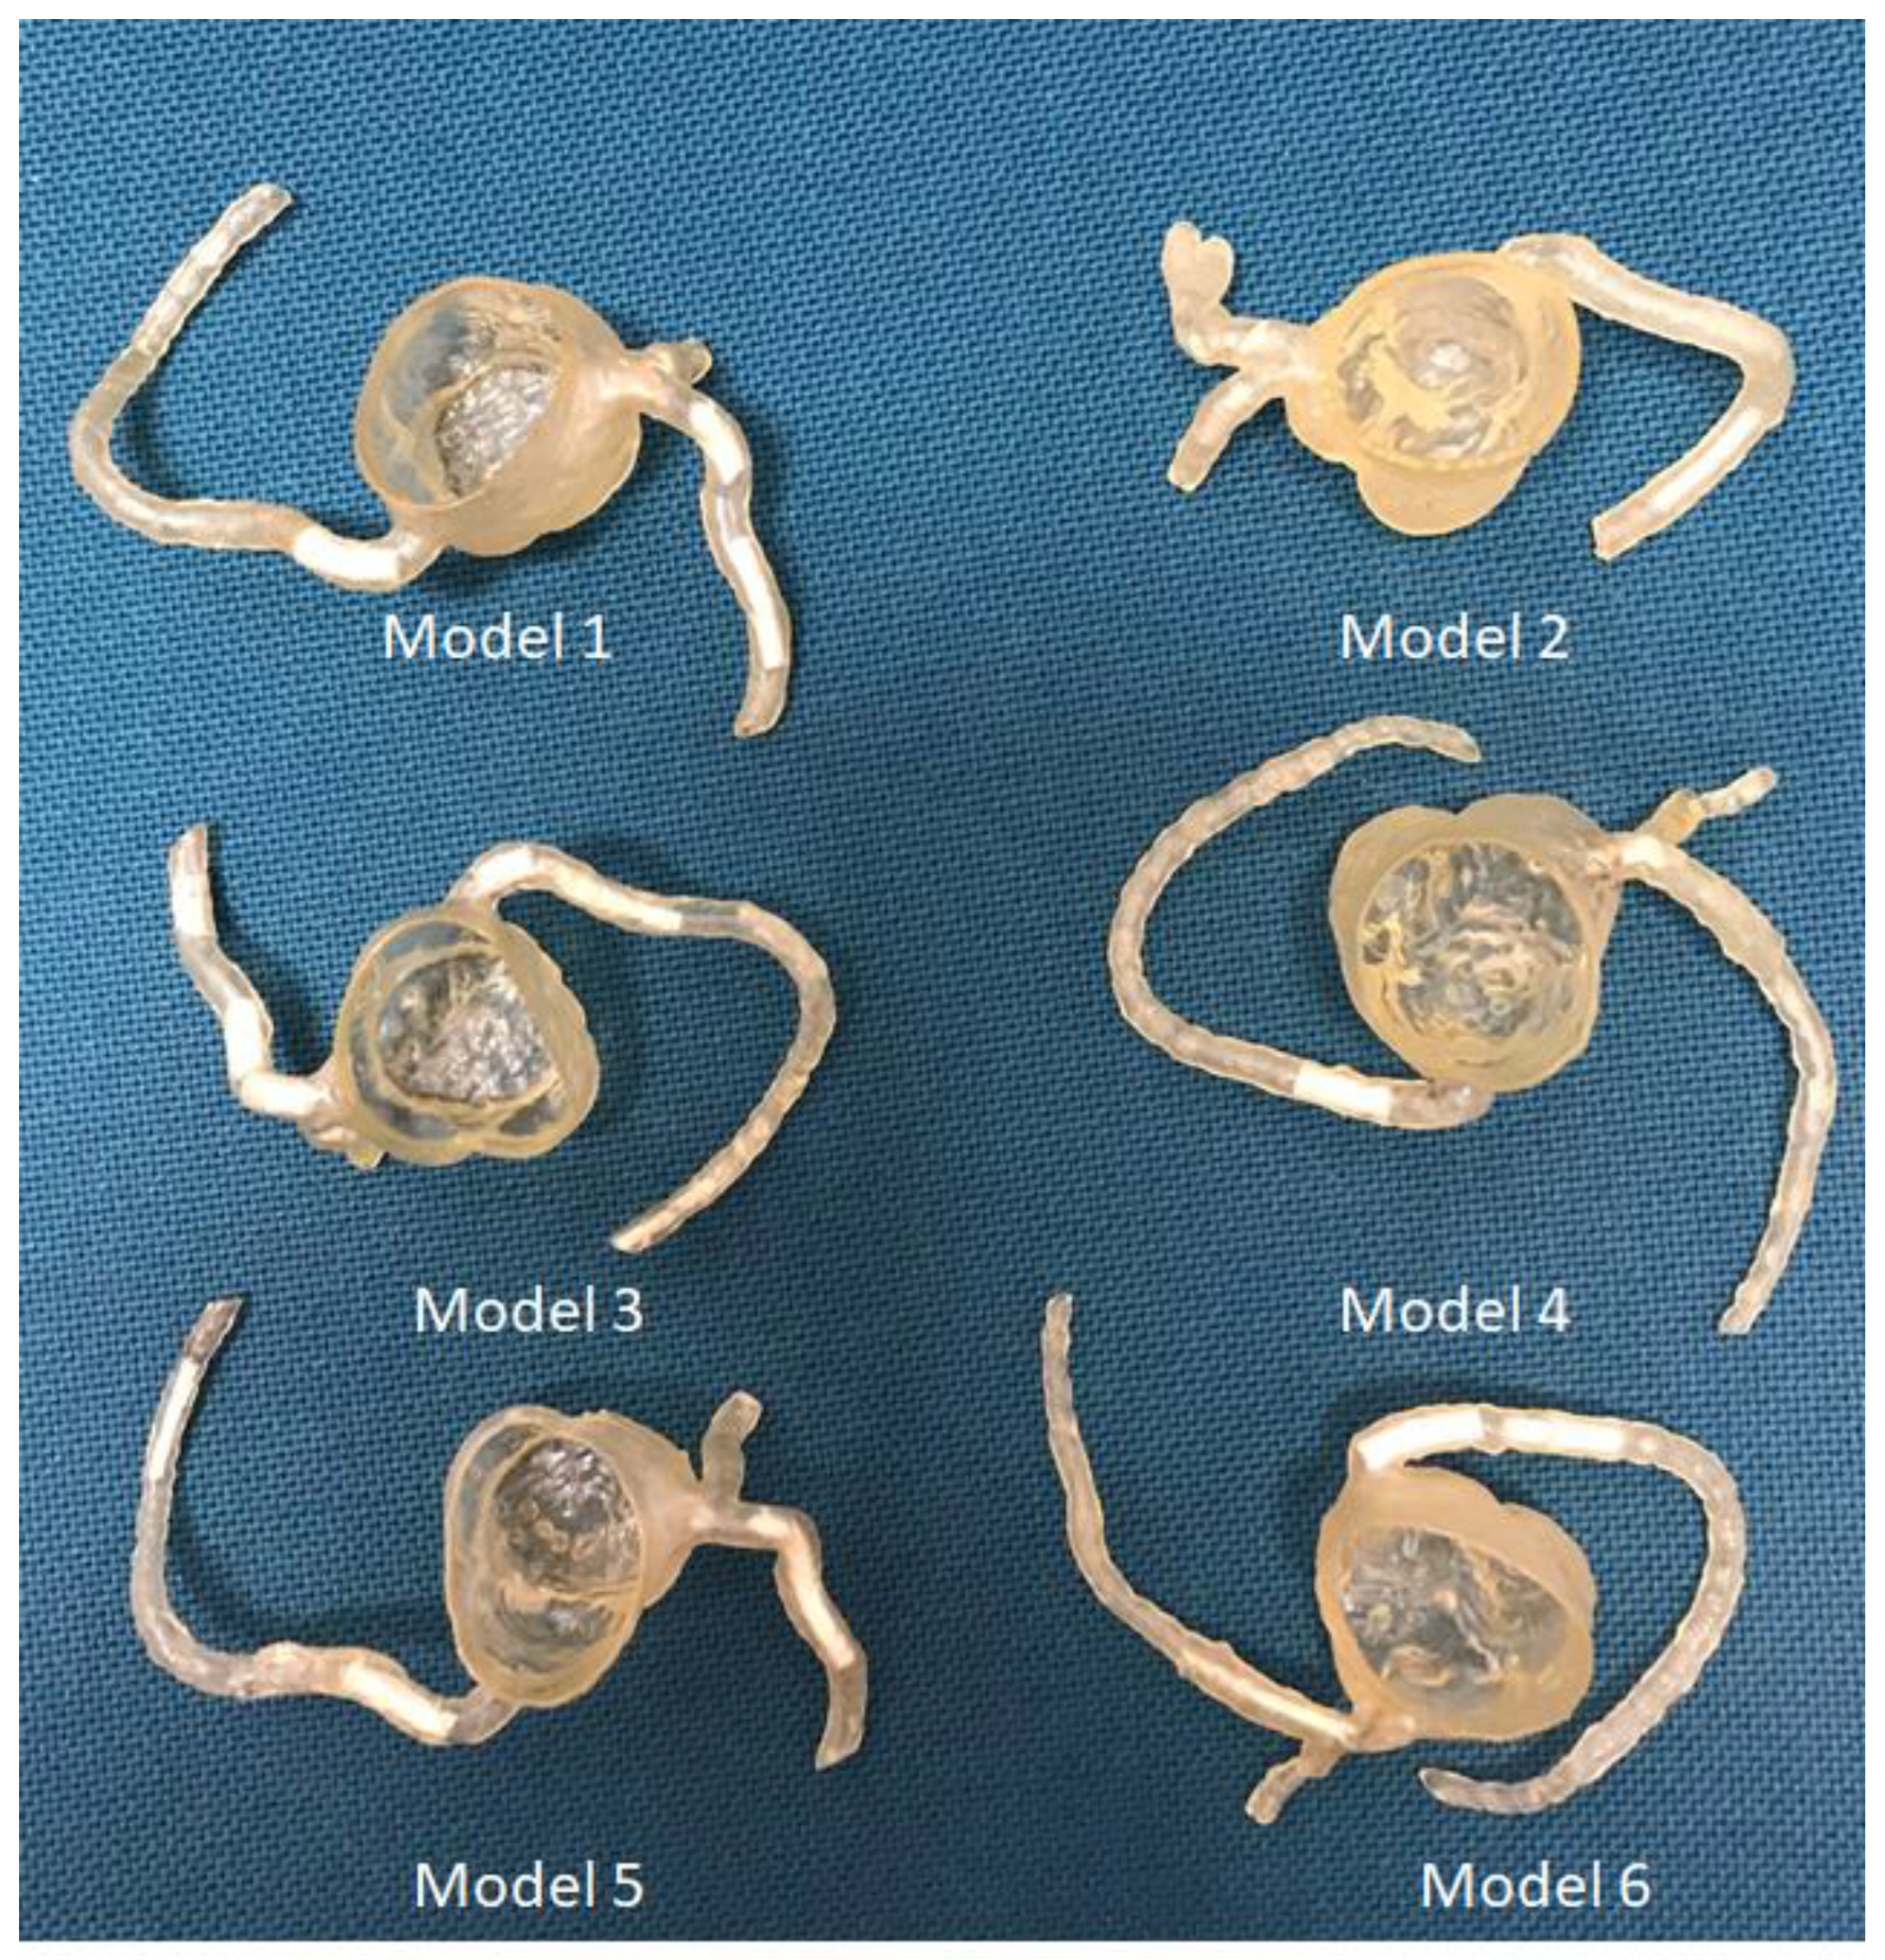

4.1. 3D-Printed CHD Model Accuracy

4.2. 3D-Printed CHD Models in Medical Education

- Lau, I.; Wong, Y.H.; Yeong, C.H.; Abdul Aziz, Y.F.; Md Sari, N.S.; Hasim, S.A.; Sun, Z. Quantitative and qualitative comparison of low- and high-cost 3D-printed heart models. Quant. Imaging Med. Surg. 2019, 9, 107–114. [Google Scholar] [CrossRef] [Green Version]